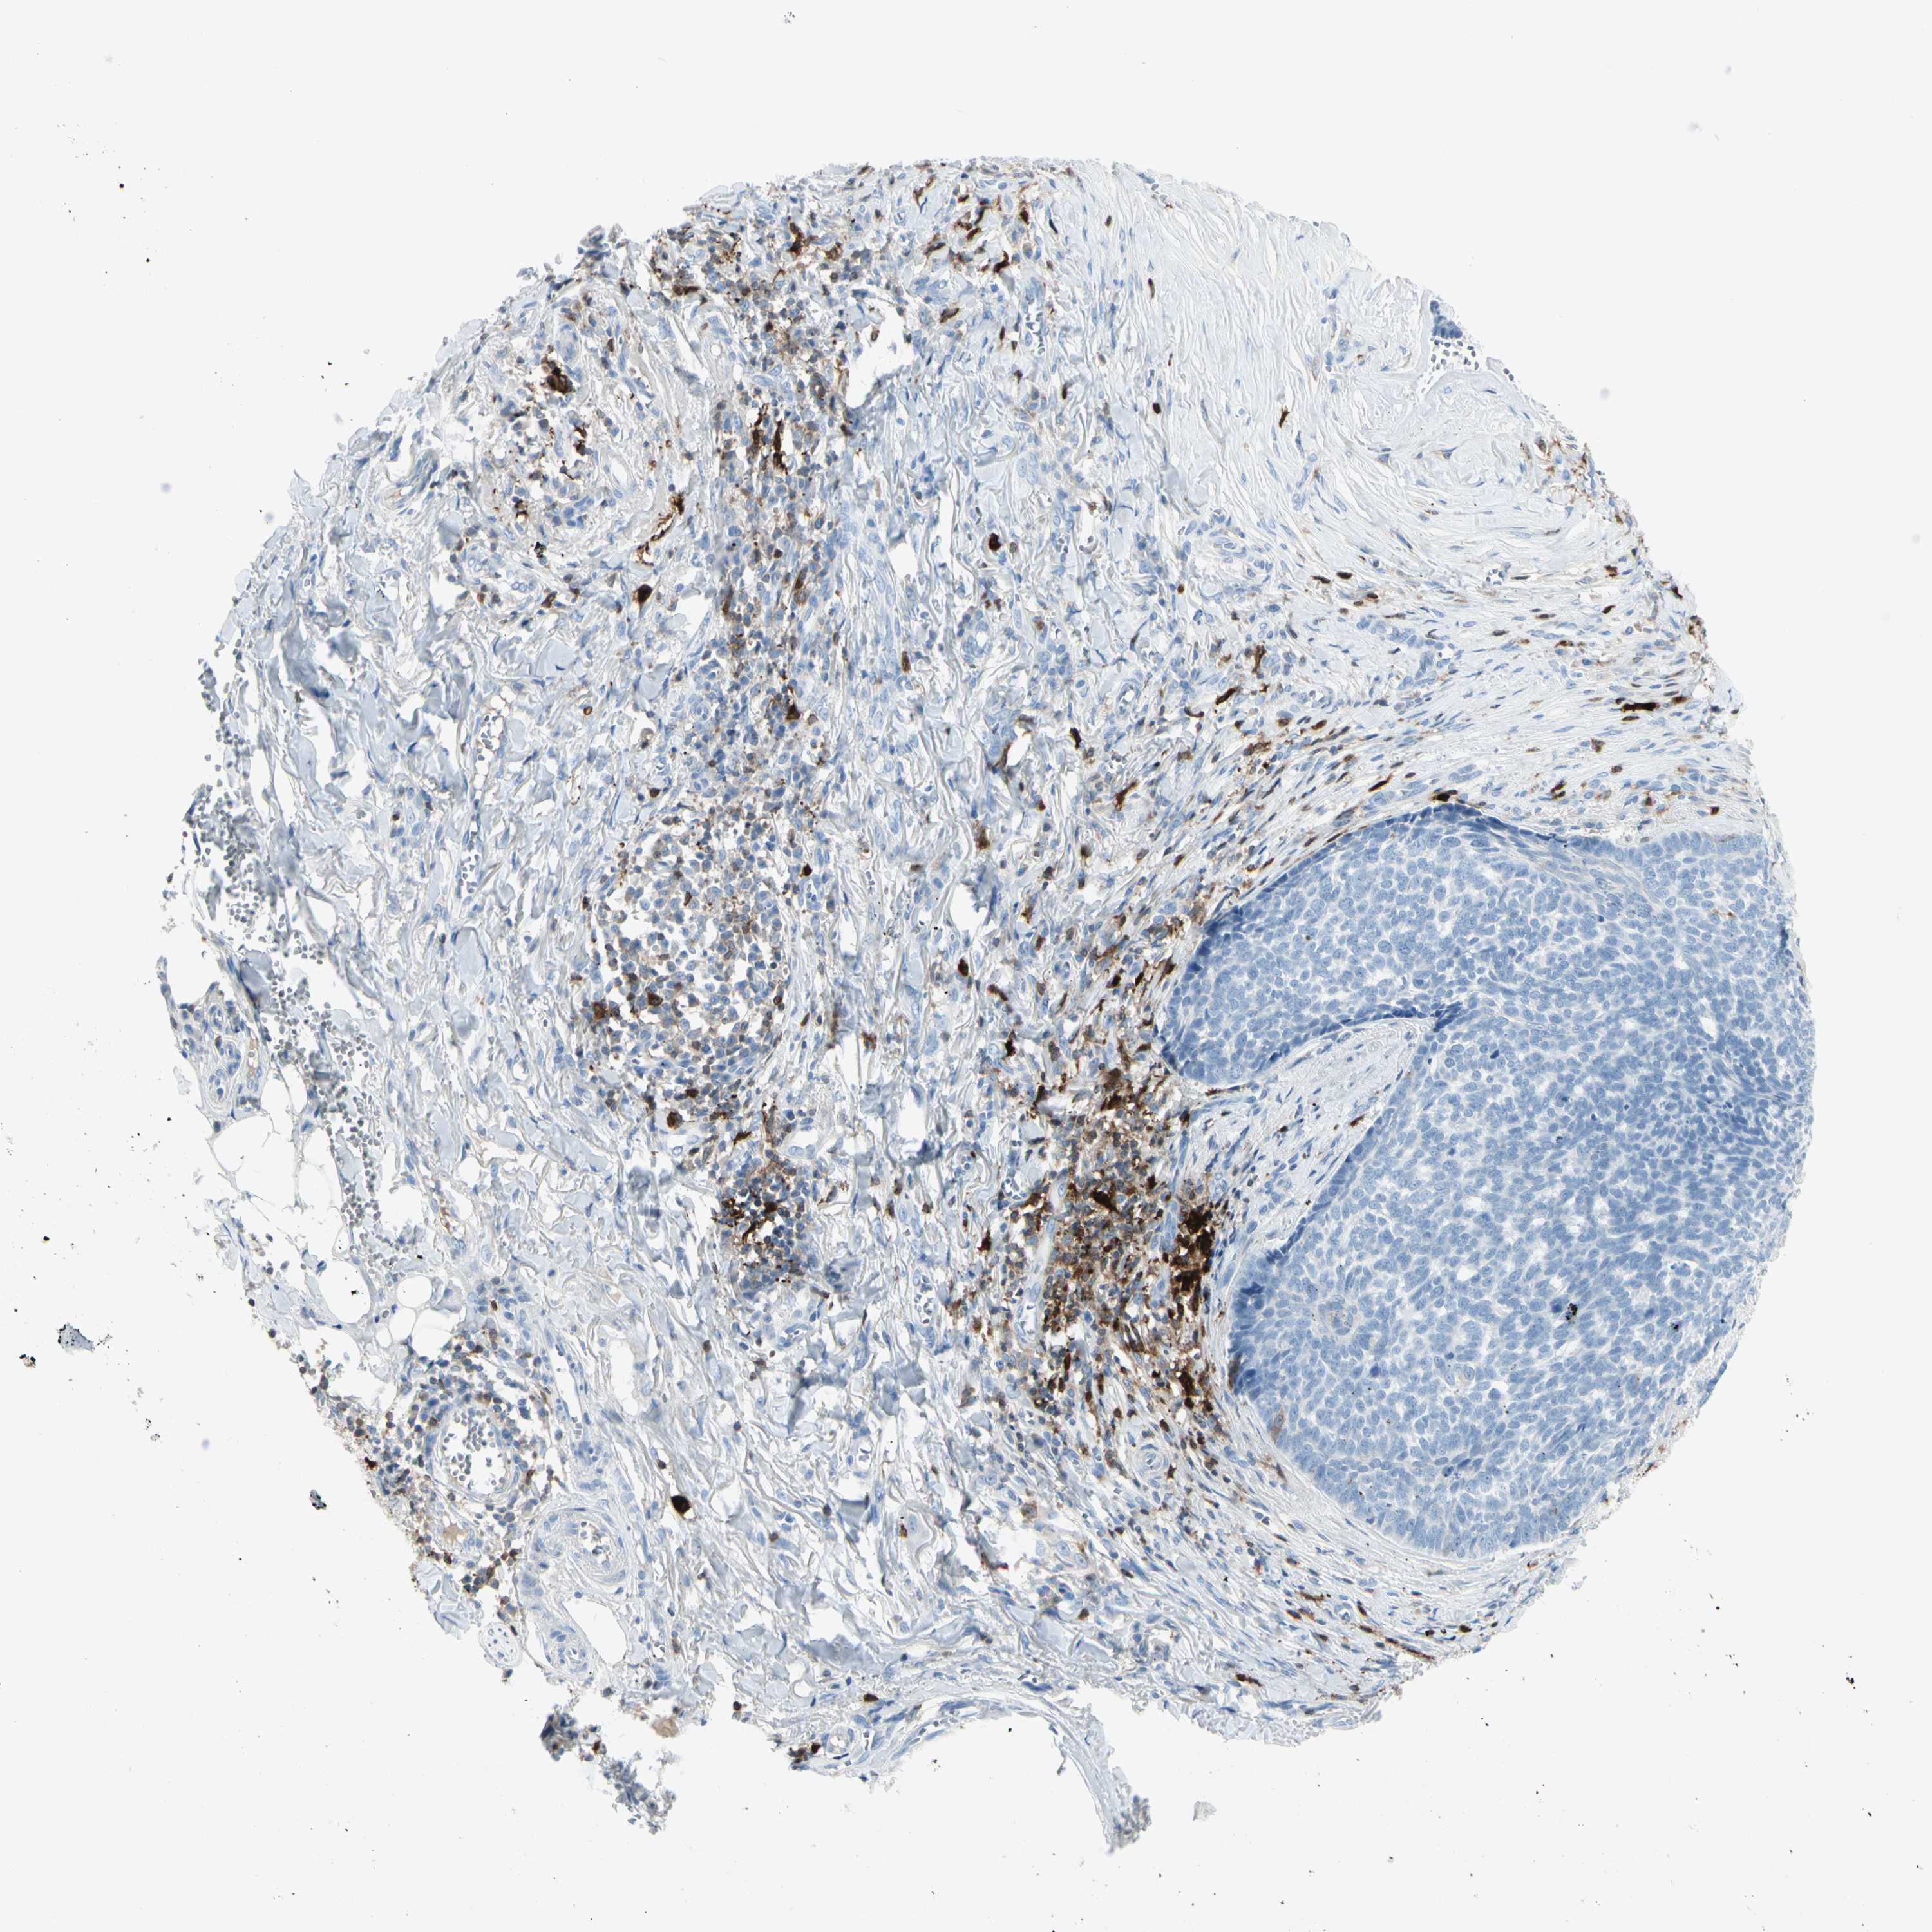

Basal cell and squamous cell cancer

SKIN CANCER - Protein expressioni

A mouse-over function shows sample information and annotation data. Click on an image to view it in a full screen mode. Samples can be filtered based on level of antibody staining by selecting one or several of the following categories: high, medium, low and not detected. The assay and annotation is described here.

Antibody stainingi

Antibody staining in the annotated cell types in the current human tissue is reported as not detected, low, medium, or high, based on conventional immunohistochemistry profiling in selected tissues. This score is based on the combination of the staining intensity and fraction of stained cells.

Each image is clickable and will lead to virtual microscopy that enables deeper exploration of all samples and also displays staining intensity scores, fraction scores and subcellular localization as well as patient and tissue information for each sample.

Antibody HPA001852

Staining

High

Medium

Low

Not detected

Intensity

Strong

Moderate

Weak

Negative

Quantity

>75%

75%-25%

<25%

None

Location

Nuclear

Cytoplasmic/membranous

Cytoplasmic/membranous,nuclear

Squamous cell carcinoma, NOS

Basal cell carcinoma